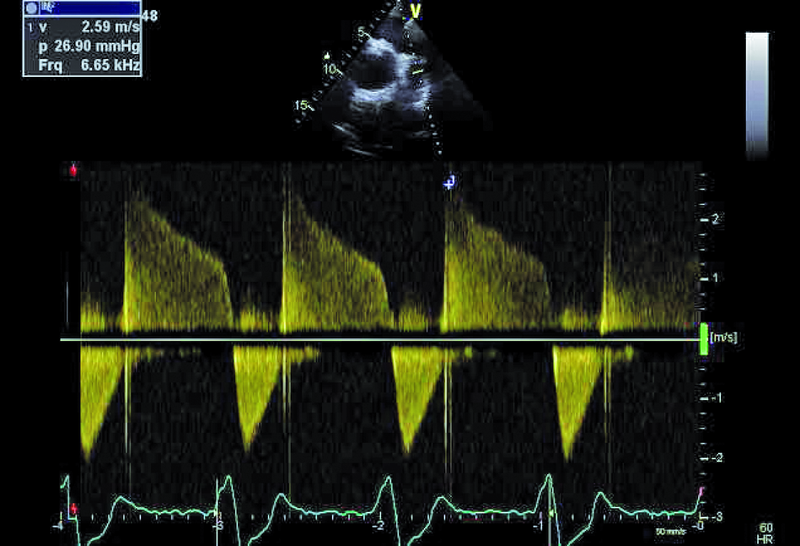

Mężczyzna, lat 35. Jakie patologie można rozpoznać na rycinach?

3. Mała stenoza zastawki płucnej (ryc. 3).

4. Niedomykalność zastawki płucnej (ryc. 3).

5. Nadciśnienie płucne (ryc. 3).